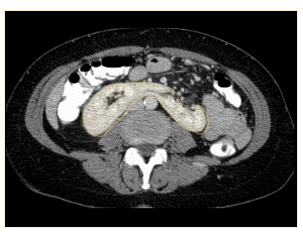

what congenital abnormality has occurred here?

A